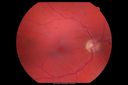

OS: Vertical C/D ratio is 0.2. There is a posterior vitreous separation. There is a pigmented lesion inferotemporal to the macula, which unfortunately does touch the fovea. It is about 9x8 millimeters high in appearance.

SPECTRALIS-SD-OCT SCAN: The photos in the right eye show the epiretinal membrane and in the left eye there is a choroidal mass. The right eye shows a partial vitreous separation with some epiretinal membrane.

The left eye shows a serous retinal detachment associated with the elevated choroidal lesion.